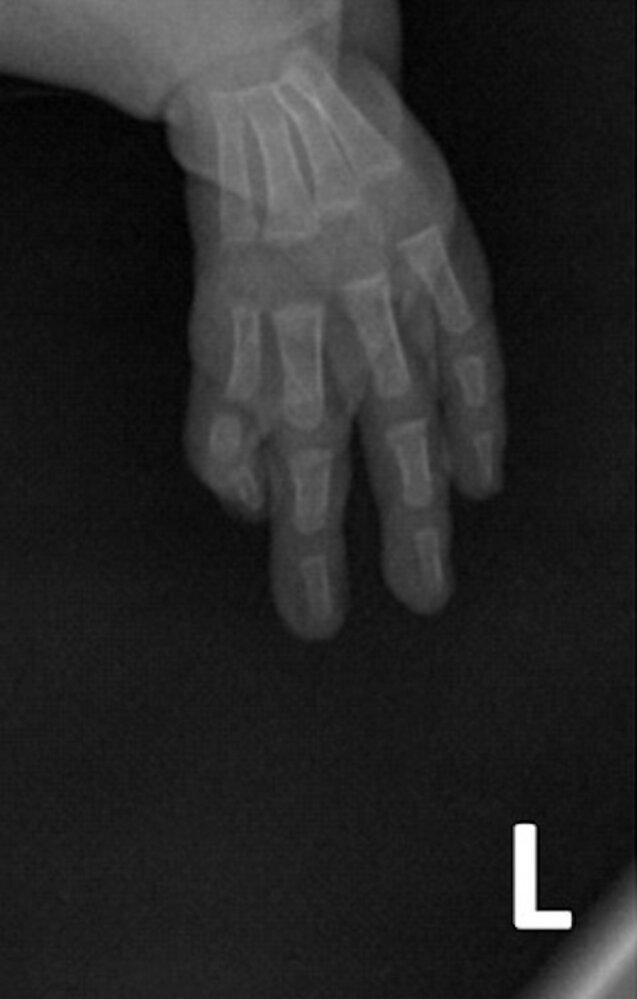

Holt-Oram syndrome (hand-heart syndrome) [3]

- Autosomal dominant disorder

- Affects ∼ 1/100,000 children

- Characterized by ASD, a first-degree heart block, and abnormalities of the upper limbs (e.g., absent radial bones)

![]()